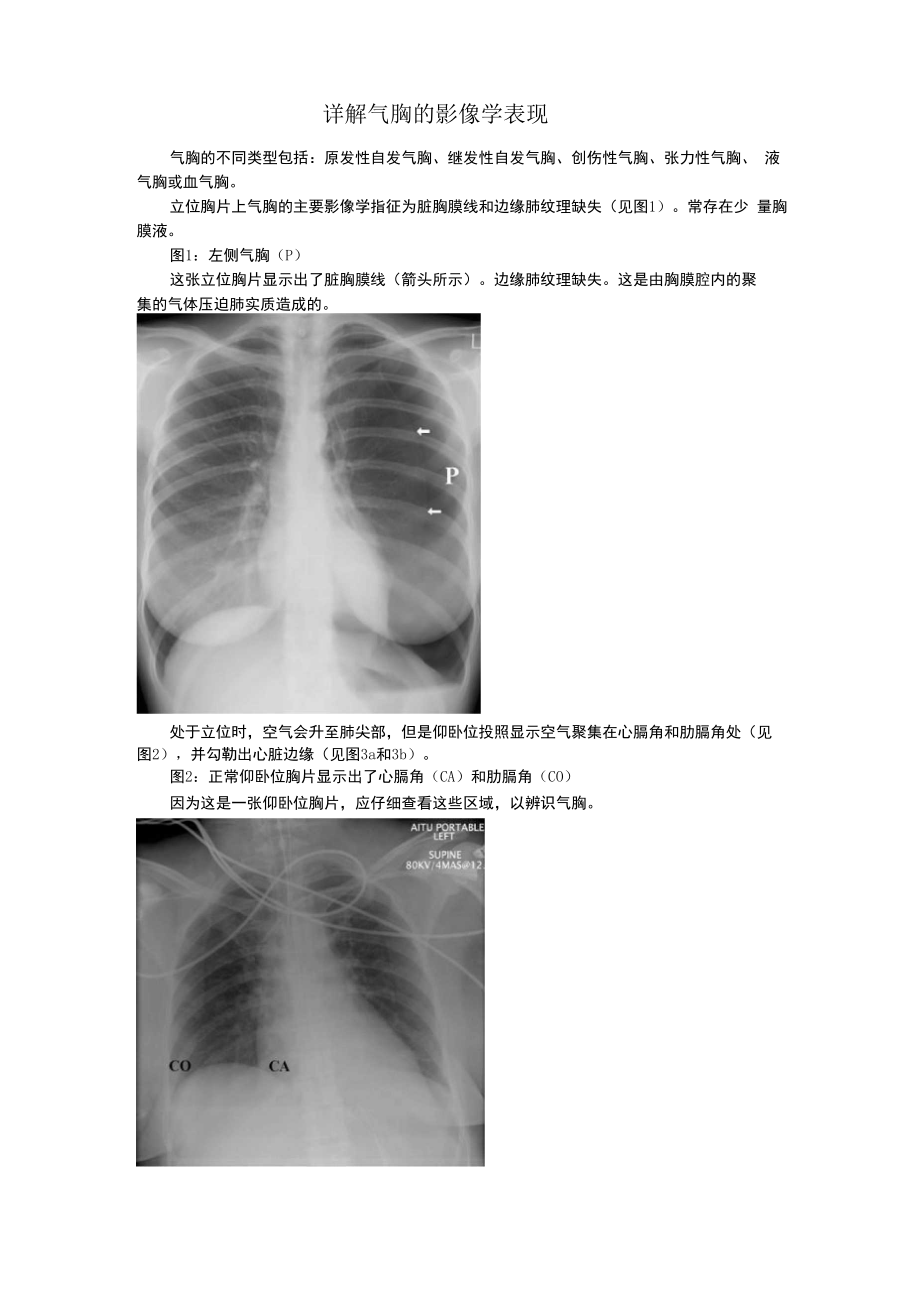

详解气胸的影像学表现气胸的不同类型包括:原发性自发气胸、继发性自发气胸、创伤性气胸、张力性气胸、 液气胸或血气胸立位胸片上气胸的主要影像学指征为脏胸膜线和边缘肺纹理缺失(见图1)常存在少 量胸膜液图1:左侧气胸(P)这张立位胸片显示出了脏胸膜线(箭头所示)边缘肺纹理缺失这是由胸膜腔内的聚集的气体压迫肺实质造成的处于立位时,空气会升至肺尖部,但是仰卧位投照显示空气聚集在心膈角和肋膈角处(见 图2),并勾勒出心脏边缘(见图3a和3b)图2:正常仰卧位胸片显示出了心膈角(CA)和肋膈角(CO)因为这是一张仰卧位胸片,应仔细查看这些区域,以辨识气胸图3a:患创伤性右气胸的插管患者的仰卧位胸片在此患者体内,空气聚集到了纵膈旁(白色箭头所示)由于空气聚集在右心缘处,因此右 心缘特别清晰(透明箭头所示)已置入右侧胸腔的引流管(箭头所示)图3b:几小时后拍摄的胸片现在,右心缘旁的空气更加明显(箭头所示)深沟征胸膜积气使肋膈角加深时,将这种形态称为深沟征(见图4)图4:对重症监护病房的机械通气患者拍摄的这张仰卧上腹部X光片显示存在左肺基 底气胸胸膜积气导致的左肋膈角(箭头所示)扩大被称为深沟征侧位X光片可能有帮助,但可能难以解读。